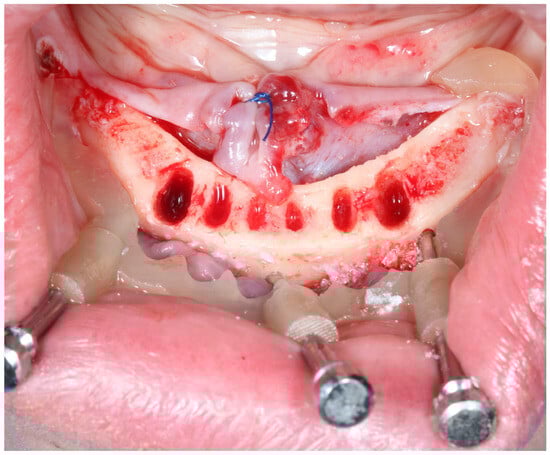

17 pages, 4799 KB

Accuracy of Computer-Guided Dental Implant Placement: A Clinical Comparison of Three Surgical Guide Types

Background/Objectives: The accurate and prosthetically driven placement of dental implants is crucial for long-term clinical success. While computer-aided static navigation enhances precision, the comparative accuracy of different surgical guide support types (teeth-, mucosa-, and bone-supported) under identical clinical conditions remains a critical [...] Read more.

Background/Objectives: The accurate and prosthetically driven placement of dental implants is crucial for long-term clinical success. While computer-aided static navigation enhances precision, the comparative accuracy of different surgical guide support types (teeth-, mucosa-, and bone-supported) under identical clinical conditions remains a critical and less explored variable. This study aimed to compare the accuracy of these three guide types. Methods: This clinical study evaluated the precision of computer-aided implant placement by comparing planned versus actual implant positions in fifty participants who received 140 implants. Discrepancies were measured in 3D using STL files in Exocad® DentalCAD software (exocad Elefsina 3.2, Darmstadt, Germany). Results: In the maxilla, mean total deviation was 0.443 mm at the implant neck and 0.562 mm at the apex. In the mandible, deviations were higher: 0.755 mm at the neck and 0.981 mm at the apex. Teeth-supported guides demonstrated the highest accuracy. Mucosa-supported guides showed the least precision, particularly in the mandible, while bone-supported guides provided clinically acceptable results. Conclusions: Computer-aided static navigation is highly accurate for implant placement. Guide selection should be tailored to anatomical conditions, with bone-supported guides preferred for edentulous mandibles. Full article

Show Figures

Figure 1